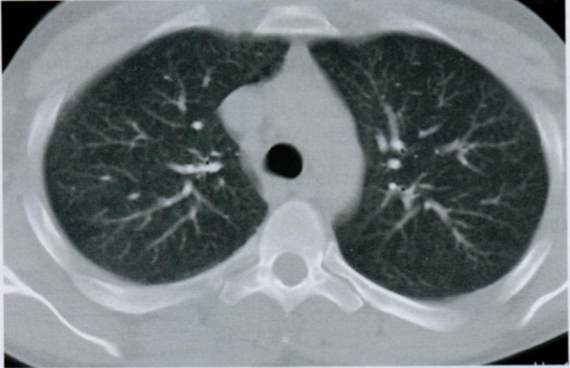

22

Q

КТ органов грудной клетки высокого разрешения.

Что Вы видите на данном КТ снимке? Постарайтесь вспомнить и назвать все анатомические структуры.

Что отмечено стрелками?

При хронических и прогрессирующих заболеваниях, когда ткань легкого становится более плотной из-за рубцевания и фиброза, податливость и вентиляция легкого уменьшается.

В результате формируется высокое стояние диафрагмы, кистозные изменения в виде “сот” и эмфизема. На ранних стадиях заболевания, когда еще нет признаков поражения на Rx, можно увидеть изменения на спирометрии и КТВР.

A

Стрелками отмечен симптом матового стекла, напоминающий воспалительную экссудацию или неопластическую инфильтрацию.

26 - грудные позвонки

24 - грудина

2 - правое предсердие

7 - восходящая аорта

9 - легочный ствол

3 - левое предсердие

10 - сосуды легких

8 - нисходящая аорта

15 - непарная вена

16 - пищевод